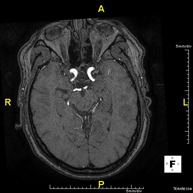

- Brain MRI (cranial)

This non-invasive diagnostic procedure uses an electromagnetic field and radio waves (from a transmitter and receiver) to acquire high-definition anatomical images of the brain. It is a radiation-free procedure. Indicated for: vascular problems, memory loss, epilepsy, headache, malformations, suspected tumour, meningitis.

- Intracranial MRI angiography

This non-invasive diagnostic procedure uses an electromagnetic field and radio waves (from a transmitter and receiver) to acquire high-definition anatomical images of the cerebral arteries. It is a radiation-free procedure. In most cases, paramagnetic contrast (gadolinium) is required. It enables non-invasive angiographic studies using a gadolinium injection, with subsequent 2D and 3D reconstruction using specialised workstations. Indicated for: vascular malformations, cerebral artery aneurysms, arteriosclerosis.